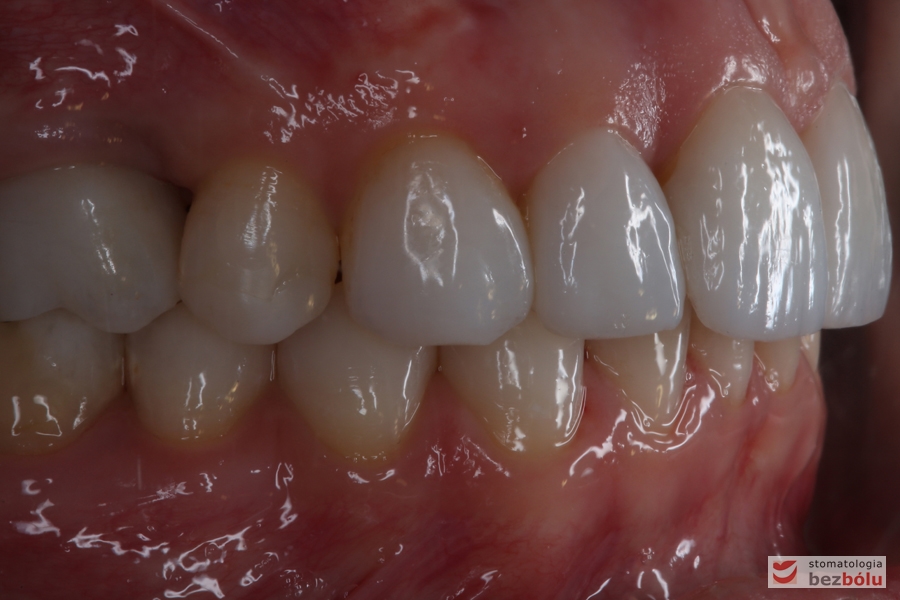

Prawa strona w zgryzie - korona prowizoryczna na pierwszym trzonowcu

Prawa strona w zgryzie – korona prowizoryczna na pierwszym trzonowcu